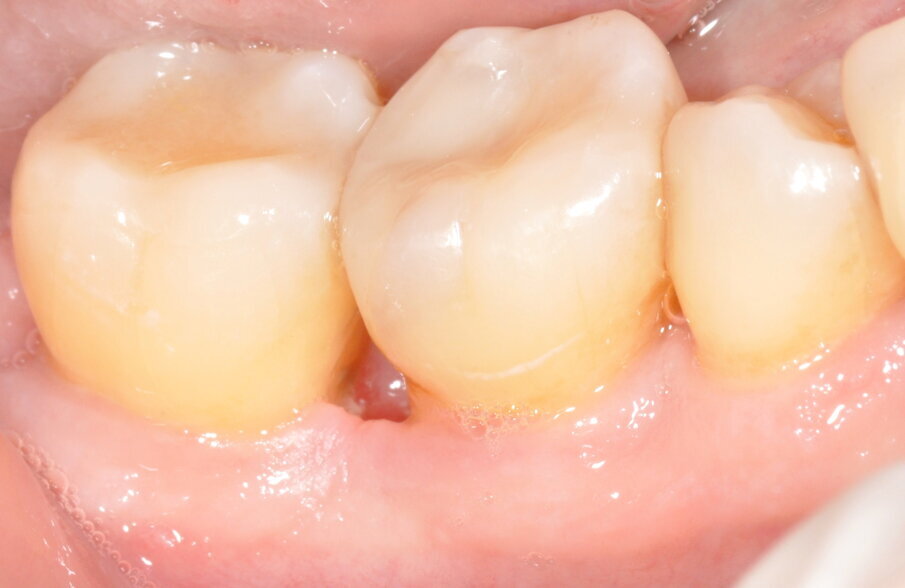

Fig. 14 - Maturazione dei tessuti e sondaggio a 3 mesi.

A 3 mesi dell’intervento il sito viene valutato nuovamente attraverso ispezione clinica e indagine radiologica; i tessuti molli risultano sani all’aspetto e al sondaggio (assenza di SOP e BOP, sondaggi MV dell’elemento 4.7 e DV dell’elemento 4.6 rispettivamente di 3 e 4 mm) ed i tessuti duri appaiono re-mineralizzati in radiografia, con il difetto intra-osseo completamente ricostruito. Distalmente all’elemento 4.6 si osservi come la papilla interdentale si sia invaginata durante il periodo intercorso tra la rimozione sutura e il controllo a 3 mesi, ciò è dovuto all’utilizzo da parte della paziente di uno scovolino di dimensioni non adeguate che viene prontamente sostituito. Anche dopo la chirurgia, la paziente rimane un soggetto con Periodontal Risk Assessment alto, a causa della perdita ossea e di elementi dentari rapportata con l’età, pertanto si inserisce in un programma di richiami trimestrali di igiene orale professionale in modo da ridurre al minimo il rischio di recidive.